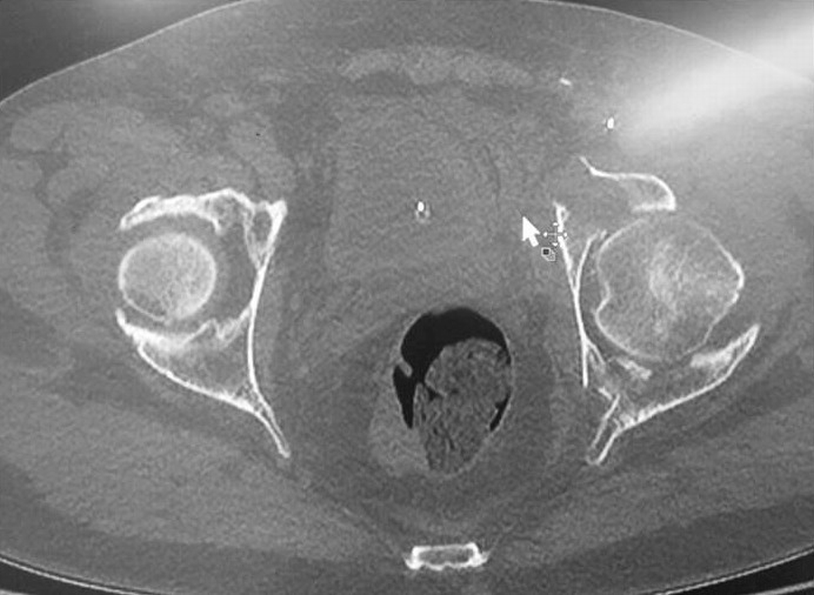

Thomas aquinas high school a roman catholic co educational college preparatory school has acquired national recognition for academic and athletic excellence. Posterior venous plexus injury in pelvic fractures can account for majority of blood loss. Corona mortis latin for crown of death is a common variant vascular anastomosis between the external iliac artery or deep inferior epigastric artery with the obturator arteryit is reported to be present in a third of patients on routine multi detector ct examination 14.

Laceration of corona mortis in 10 15. Knowledge of this variant vascular anastomosis is critical for surgical planning and in pelvic trauma as it is. 82 34954251 l 2 b select answer to see preferred response.

Connection between inferior epigastric branch of the external iliac vessls and the obturator vessels. Exposed and retracted early in the exposure. Lateral in comparision to tibial division most commonly injured neural structure during tha.